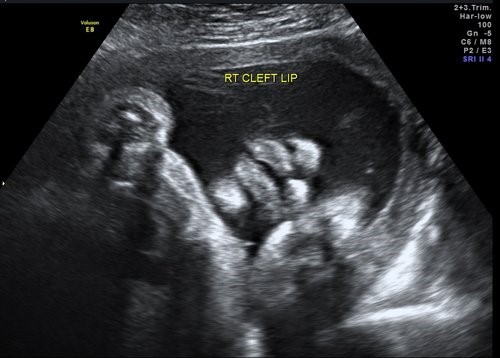

Cleft Lip & Cervical Teratoma

CERVICAL TERATOMA

Sonovision Ultrasound